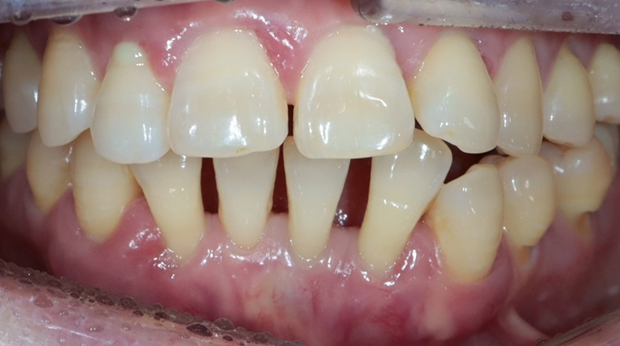

구강외과 진료

라미네이트

매복 사랑니 발치

의식하진정법(수면마취)/임플란트